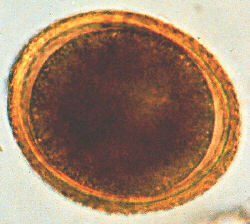

Refer to the picture above for question 3. |

3. Related features in this boy include::